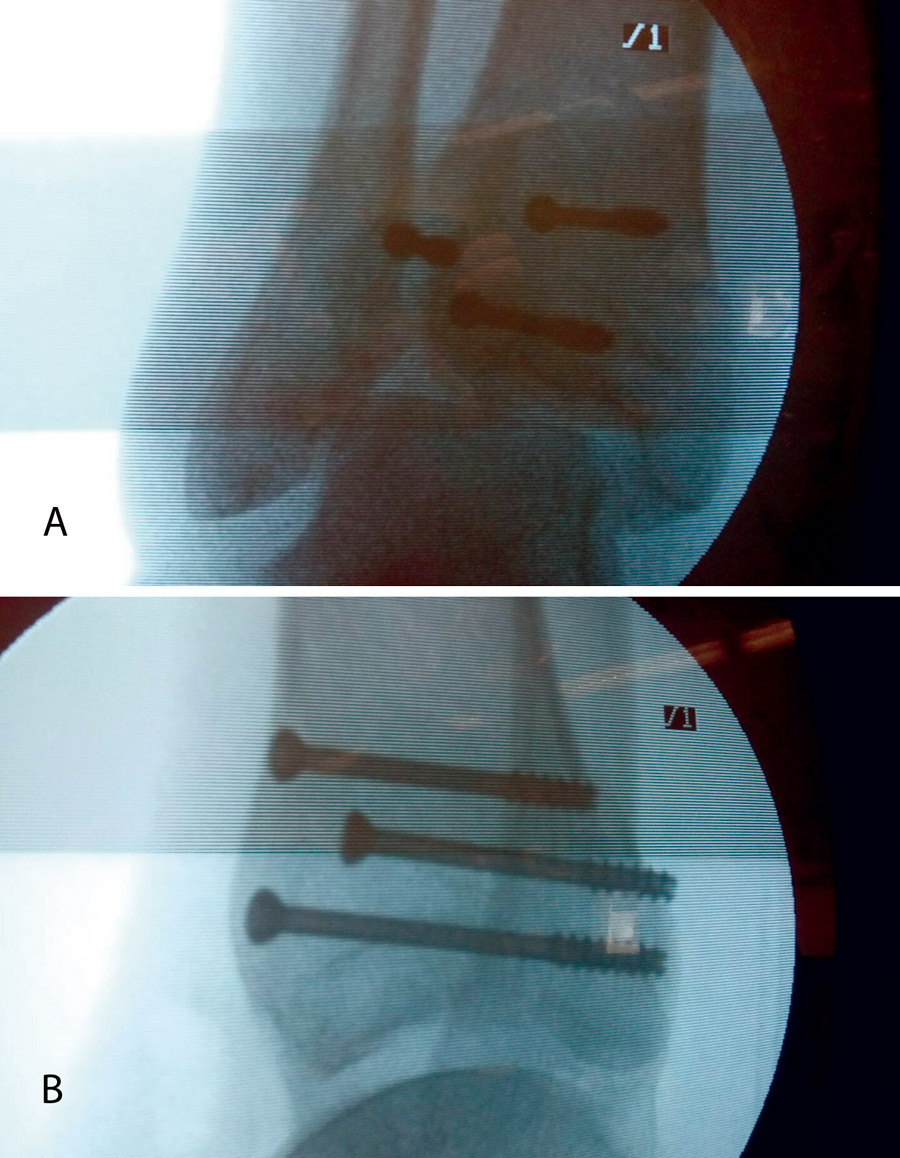

Figura 14. A continuación, se realiza la medición y colocación secuencial de los tornillos.

Figura 15. Por último, se procede a la colocación definitiva de los tornillos.

Figura 16. Resultado final a los 4 meses.